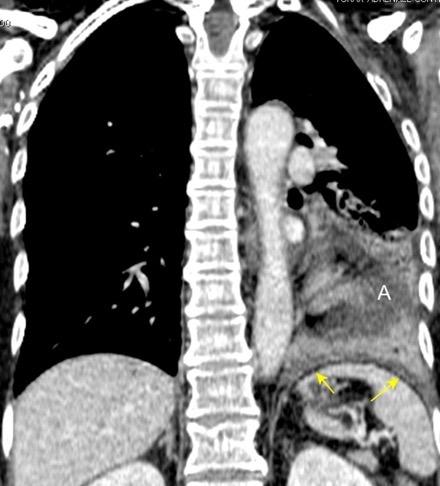

T. mixto de células germinales del testículo izquierdo

Nódulos pulmonares múltiples. (flechas verdes). Masas paratraqueales. (flechas amarillas). Dudoso ensanchamiento retrocrural (flechas negras). sigue….

T. mixto de células germinales del testículo

izquierdo Metástasis pulmonares. (flechas verdes). Ganglios paratraqueales. (flechas amarillas). Ganglios retroperitoneales (flechas negras)

Tawfik A et al. Trans-diaphragmatic Pathologies: Anatomical Background and Spread of Disease on cross-sectional Imaging. Current Problems in Diagnostic Radiology. 2021.